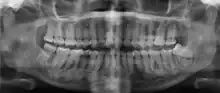

| Florid osseous dysplasia of the mandible | |

Cemento-osseous dysplasia (COD) is a benign condition of the jaws that may arise from the fibroblasts of the periodontal ligaments. It is most common in African-American females. The three types are periapical cemental dysplasia (common in those of African descent), focal cemento-osseous dysplasia (Caucasians), and florid cemento-osseous dysplasia (African descent). Periapical occurs most commonly in the mandibular anterior teeth while focal appears predominantly in the mandibular posterior teeth and florid in both maxilla and mandible in multiple quadrants.